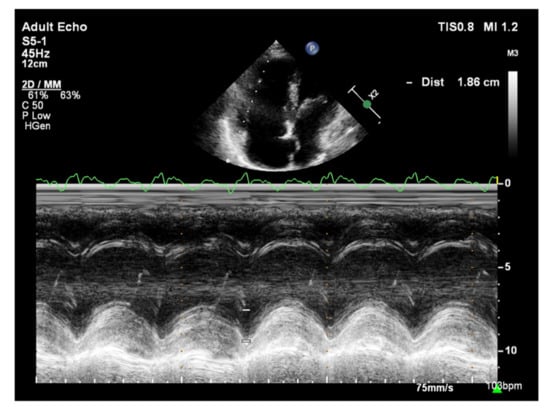

The longitudinal fibers of the right ventricular muscle are mainly responsible for muscle contraction. Contraction of these fibers also causes movement of the tricuspid valve annulus, which moves toward the ventricular apex in systole and toward the atrium in diastole [37]. Therefore, the amplitude of tricuspid annular systolic motion (TAPSE), obtained by the M-mode technique from the 4CH view, reflects RV systolic function (Figure 8) [37]. TAPSE values <18 mm are associated with poor prognosis and higher mortality in patients with PAH [38]. A correlation between TAPSE and RV ejection fraction (RVEF) measured by radionuclide angiography has also been demonstrated [39]. Considering that the TAPSE measurement is uncomplicated, highly reproducible, has little dependence on image quality, and has a high prognostic value, it is recommended that TAPSE is determined in all patients with PAH to assess RV systolic function [2]. However, TAPSE has a disadvantage of being angle-dependent and may be overestimated with apical rocking [40]. In addition, TAPSE may be load-dependent [41].

Figure 8.

Patient with PAH, TAPSE = 1.86 cm. TTE, M-mode. PAH: pulmonary arterial hypertension; TAPSE: tricuspid annular plane systolic excursion; TTE: transthoracic echocardiography.